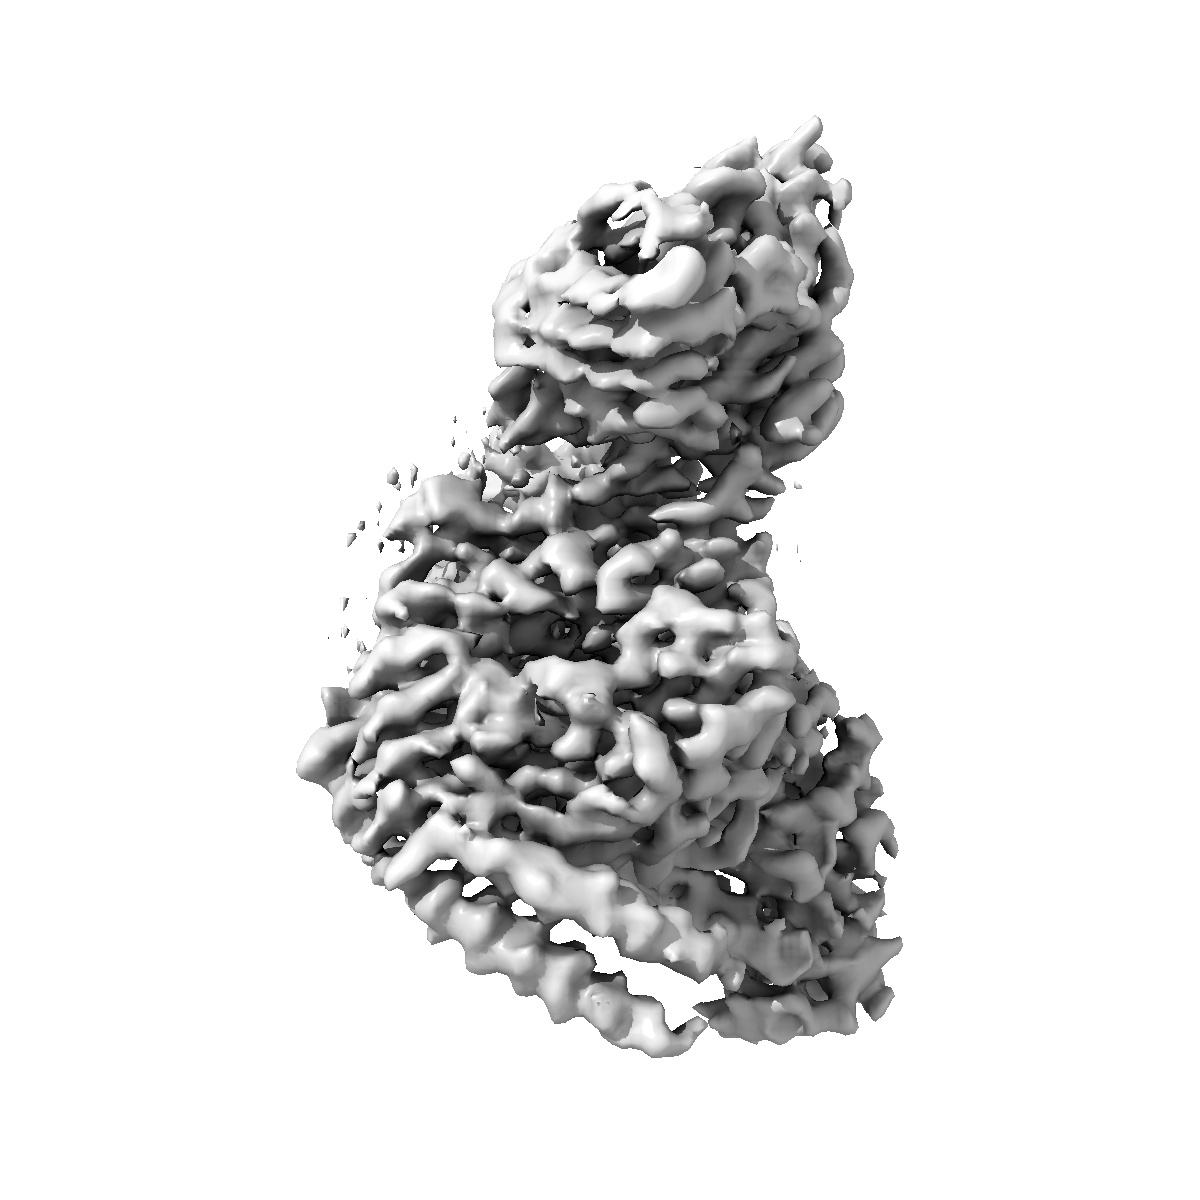

Cryo-EM structure of PTH-PTH1R-Gq complex (tilted state; consensus refinement map)

Single-particle2.77 Å

Sample: PTH-PTH1R-Gq complex

Insights into G-protein coupling preference from cryo-EM structures of G q -bound PTH1R.

(2025) Nat Chem Biol , 21 , 1906 - 1914